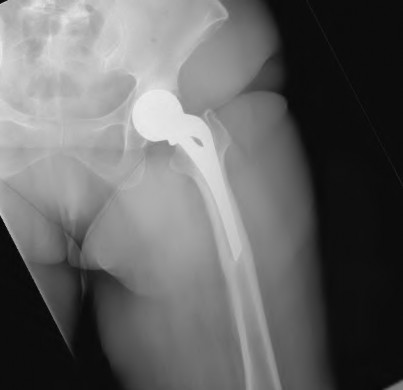

A 72-year-old female presents with progressive left thigh and knee pain for the last year. 5 years ago she sustained a femoral neck fracture treated with the implant seen in Figures A-C (current radiographs). The thigh pain is worse with weight-bearing. C-reactive

protein and erythrocyte sedimentation levels are within defined limits. Which of the following is the most likely cause of her pain?